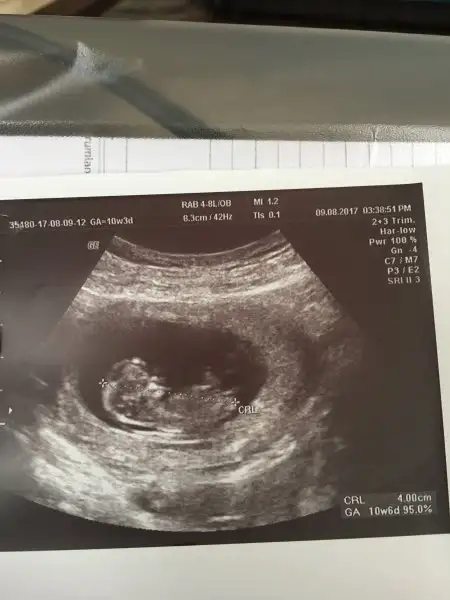

Merhaba sizde ultarson fotoğrafını atsanız olurmu, görüntüler nasıl , tahminlerde bulunan arkadaşlar belki yardımcı olurlar, hem kız tahminli bebeklerle , görüntü farkı varmı bizlerde anlasak.